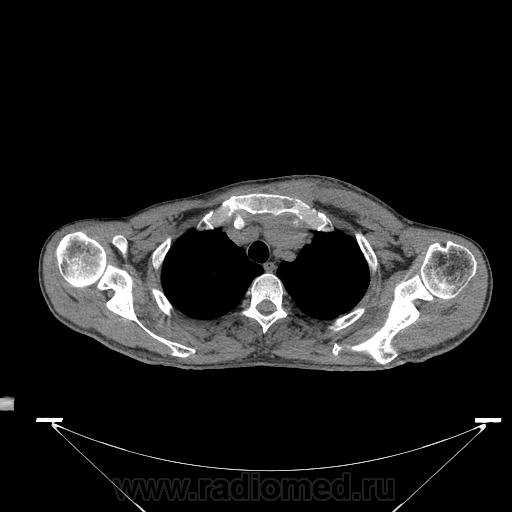

Миелома (плазмоцитома).

Недавний случай. Подтвержден гистологически.  По сцинтиграфии дополнительные очаги гиперфиксации РФП с некоторых ребрах и крестцово-подвздошных сочленениях.